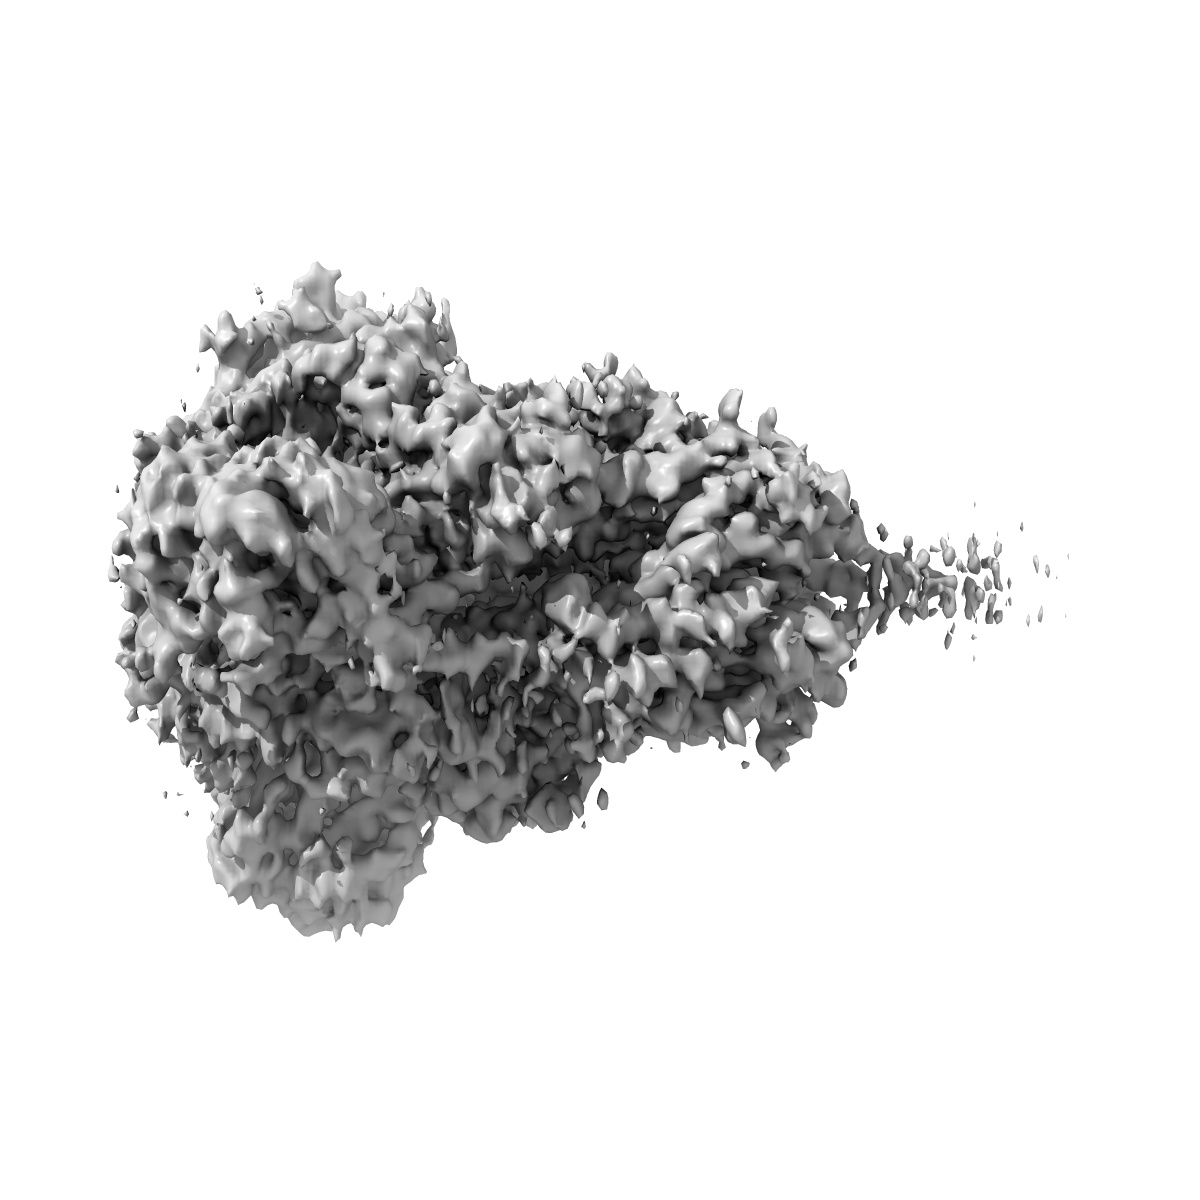

Cryo-EM structure of MERS-CoV spike protein, all RBD-down conformation

Single-particle4.1 Å

Sample: recombinant MERS-CoV (betacoronavirus 2c EMC 2012) fm2P Spike

Fitted models: 7yn0